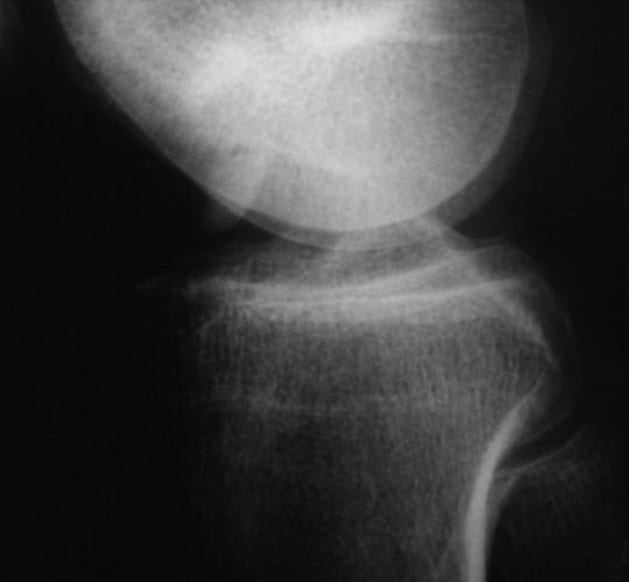

MRI preoperative

Free joint body lies intercondylar. Clear joint effusion and deep and free mouse bed visible.